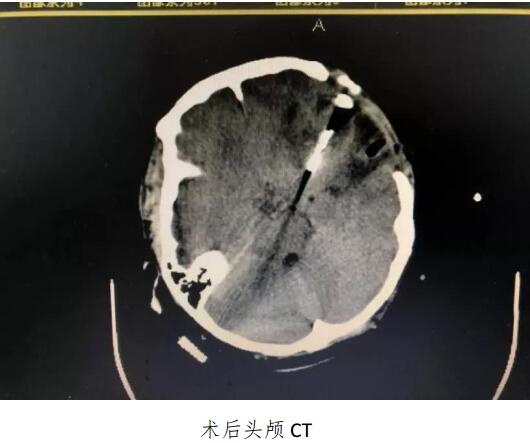

啄木鸟 成功开展颅内动脉瘤夹闭术及脑血管造影动脉瘤栓塞术